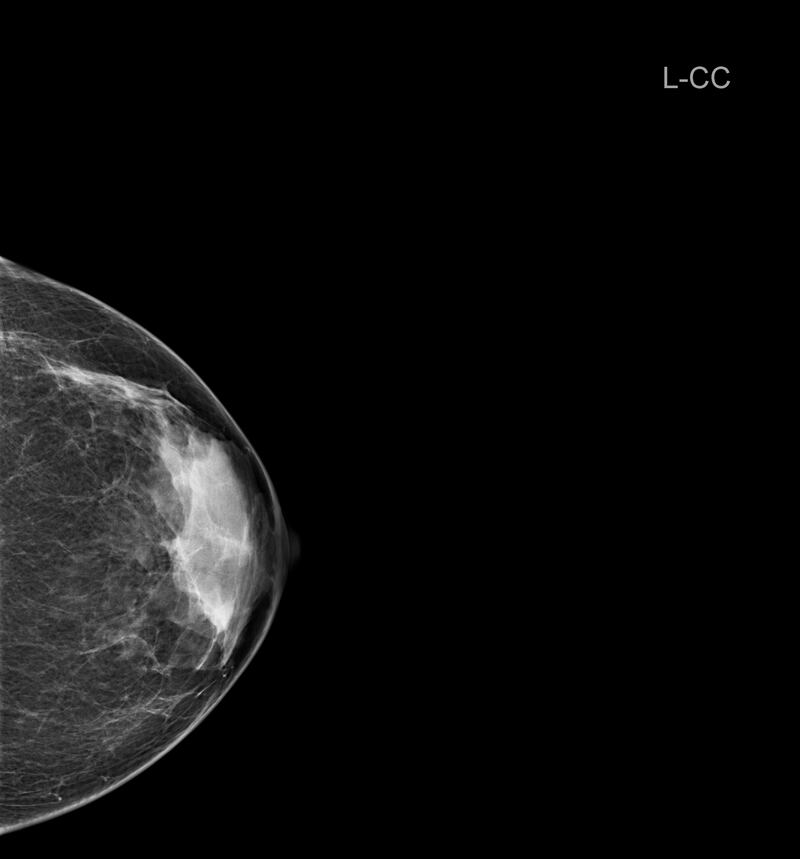

¿Qué es una mamografía?

“Una mamografía es una imagen de la mama tomada con rayos X que permite ver una imagen del interior de los senos. Existen mamografías de detección y mamografías de diagnóstico. Al realizarse una mamografía como especialista puedo detectar irregularidades en la mama o tumores que aún no se pueden sentir”, cuenta Clayreth Vinueza especialista en radiología.

Para la experta una mamografía debe realizarse a partir de los 40 años una vez todos los años. Además, que en mujeres con antecedentes de cáncer de mama o de varios se recomienda comenzar antes.